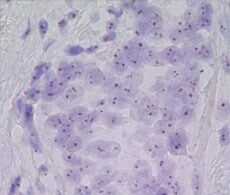

显色原位杂交 (CISH) 能让您利用组织学实验室中已经存在的方法在组织形态学背景下获取遗传信息。 我们提供用于CISH分析的CISH DNA探针和关键试剂。